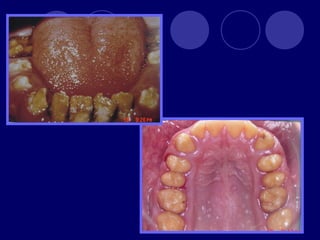

DENTINOGENESIS IMPERFECTA TIPO I:asociada a padecimiento esquelético, asociada a osteogénesis imperfecta (escleróticas azules, sordera, múltiples fracturas,etc.)  Dos denticiones  Dientes blandos, consistencia terrosa  Rx: cámaras pulpares obliteradas

TIPO II:  Dientesde color: amarillo, pardo azulado u opalescente con brillo translúcido, raíces color ámbar  Rx: coronas bulbosas, cámaras pequeñas o ausentes, raíces delgadas y cortas TIPO III: (SHIELDS)  Temporal: translúcido, ámbar  Permanente: normal

OSTEOGENESIS IMPERFECTA Alteración deesmalte y dentina En la dentición temporal no hay esmalte y dentina muy abrasionada En la dentición permanente esmalte frágil color grisáceo y amplias zonas desprovistas de éste, dentina atípica